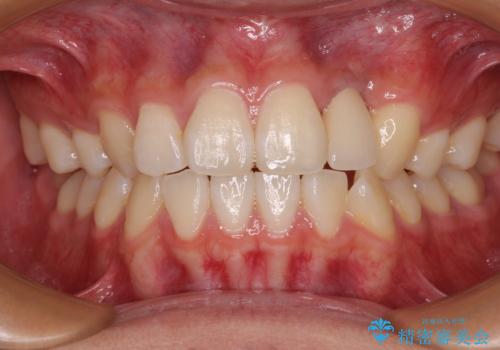

抜歯と言われた前歯 牽引してセラミッククラウンで保存する

- 他院で前歯の抜歯が必要と言われたとのことで来院された患者様です。

過去にぶつけたことで神経組織が壊死してしまったようで、その後むし歯が進行して歯肉深いところにまで進んでいる状態でした。

まずは部分矯正により歯を牽引し、歯肉や歯槽骨の位置を調整するために歯周外科処置を行い、治癒を待ってオールセラミッククラウンにて補綴治療を行うこととしました。

しっかりとむし歯を牽引したことで、クラウンの周りの腫れが引き、自然な口元に仕上げることができました。